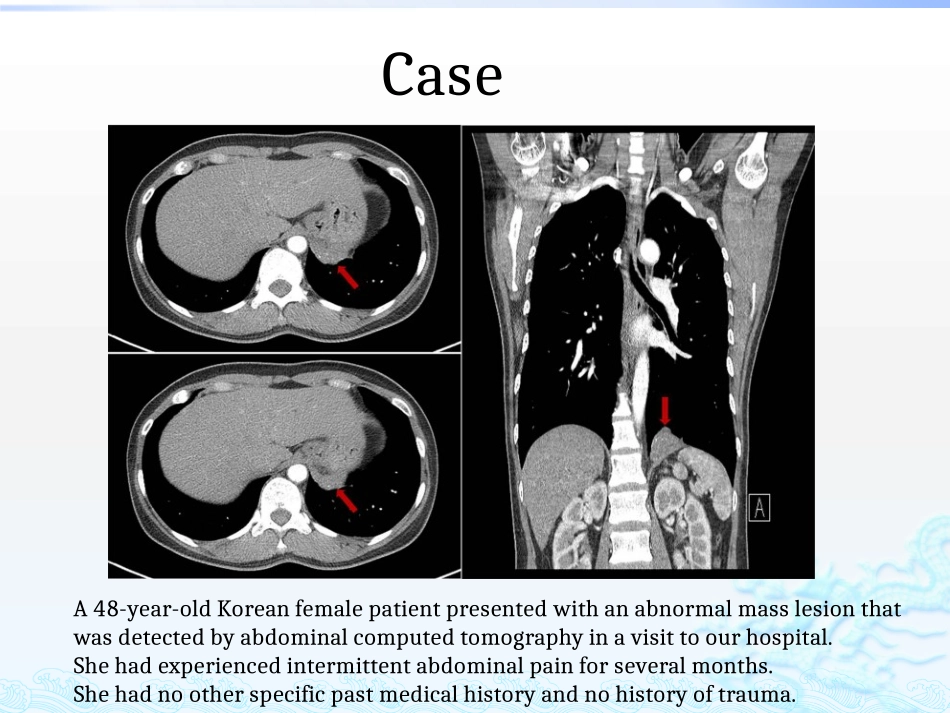

肺隔离症影像学诊断A48-year-oldKoreanfemalepatientpresentedwithanabnormalmasslesionthatwasdetectedbyabdominalcomputedtomographyinavisittoourhospital.Shehadexperiencedintermittentabdominalpainforseveralmonths.Shehadnootherspecificpastmedicalhistoryandnohistoryoftrauma.Case10/23/202409:42AM3男性,46岁。反复咳嗽、咳痰多年。胸片及CT,诊断为左下肺支扩并感染、左下肺化脓性病变等。(A)Incisionofdiaphragm(blackarrow),Intradiaphragmaticmass(redarrow)wasidentified.(B)Diaphragmaticbulge(blackarrow).Incisionsiteofdiaphragm(redarrow).(C)Smallaberrantvesselswereclipped(blackarrow).(D)Yellowishmucoidmaterialsweredrained(blackarrow)(A)Grossfindings.(B)Dilatedmucin-filledairwaysandremnantsofcartilaginousbronchi(x100,hematoxylinandeosinstain).(C)Normallungtissueisnotobserved(x100,hematoxylinandeosinstain).(D)Dilatedairwaysarelinedbybronchiolartypeepithelium(x200,hematoxylinandeosinstain).肺组织与支气管树缺乏交通的先天性畸形,从而与其余肺分离,并由体循环动脉供血。定义较为常见的肺的先天性发育异常,占肺部疾病的0.15%~6.4%.肺隔离症可见于各年龄段,以青年人居多多数无症状,合并感染则可表现为呼吸道感染的症状,可有发热、咳嗽、咳痰、胸痛、甚至痰中带血的症状。叶内型多于叶外型,左侧多于右侧。病因在胚胎发育期间,动脉发育不全使一部分肺组织血液供应受障碍,并由主动脉的分支代替动脉供应该区组织,由于来自主动脉的血液含氧量与来自肺动脉的血液完全不同使该段肺组织的肺功能无法进行,因而发育不全,而无肺功能。叶内型位于脏胸膜组织内,其囊腔病变与正常的支气管相通或不相通,临床多见叶外型2.后者被自己的胸膜包盖,独立于正常肺组织之外,囊腔与正常支气管不相通。多见,占75%近2/3的叶内型位于左下叶后段脊柱旁沟内,其余的位于右下叶相应部位,上叶很少受累。血液供应主要来自降主动脉及腹主动脉,静脉主要回流入肺静脉。多与支气管相通,常发生反复感染,感染多为化脓性,表现为咳嗽、咳痰、发热,感染严重时可有大量脓痰,咯血和气短。叶内型90%的叶外型位于左半膈,可位于下叶与膈肌间、膈下,膈肌内或纵膈中。血液供应通常来自腹主动脉,静脉回流通常经由下腔静脉、奇静脉或门静脉系统。与支气管不相通,临床上常无症状,多在胸部影像学检查、尸检或合并其他畸形时被发现。叶外型病理叶外型有独立的胸膜包裹,与正常组织完全分隔。叶内型分布于正常肺组织内,与正常肺有薄层结缔组织相隔。可与正常支气管相通或不相通。镜下隔离肺组织可有不同程度的肺不张、炎症和纤维化。支气管腔内有纤毛柱状上皮,管壁有小软骨片和平滑肌,部分支气管和肺泡扩张形成囊腔及支气管扩张。血管结构为肌型体动脉和静脉,没有肺内弹力肌型动脉。下叶肺后基底段内,有单个或多发的圆形、卵圆形等囊性病变阴影。囊壁厚薄不等,周围有炎变影像。确诊较难诊断X线片检查:左下肺隔离症CT诊断依据叶内型蜂窝状、大小不等含液囊状或软组织密度肿块,少数见钙斑,脓肿形成叶外型边界清楚、密度均匀软组织肿块,少数见多发小囊增强检查不规则强化,可显示供血动脉和引流静脉CT检查:可较清楚显示病变形态,还可确认异常动脉存在的典型表现。正常肺支气管动脉和静脉束远离或围绕在隔离肺叶外周,偶见钙化。如与支气管树交通造成感染,其表现为含气囊肿,有或无液平,周围可见炎性浸润,也可呈囊肿样表现可有气液平。但诊断阳性率并不高。10/23/202409:42AM2010/23/202409:42AM2110/23/202409:42AM2210/23/202409:42AM2310/23/202409:42AM2510/23/202409:42AM26边界清楚,囊性区长T1、长T2信号,实性中等T1、长T2信号,均匀/不均匀;多平面成像有助于显示解剖关系、供血动脉和引流静脉,有助于区分叶内/叶外型MRI:10/23/202409:42AM2710/23/202409:42AM281.异常动脉穿出膈肌自右肺下叶膈面入肺。2.切断并缝扎异常动脉血管10/23/202409:42AM293.切除右肺下叶4.标本造影效果10/...